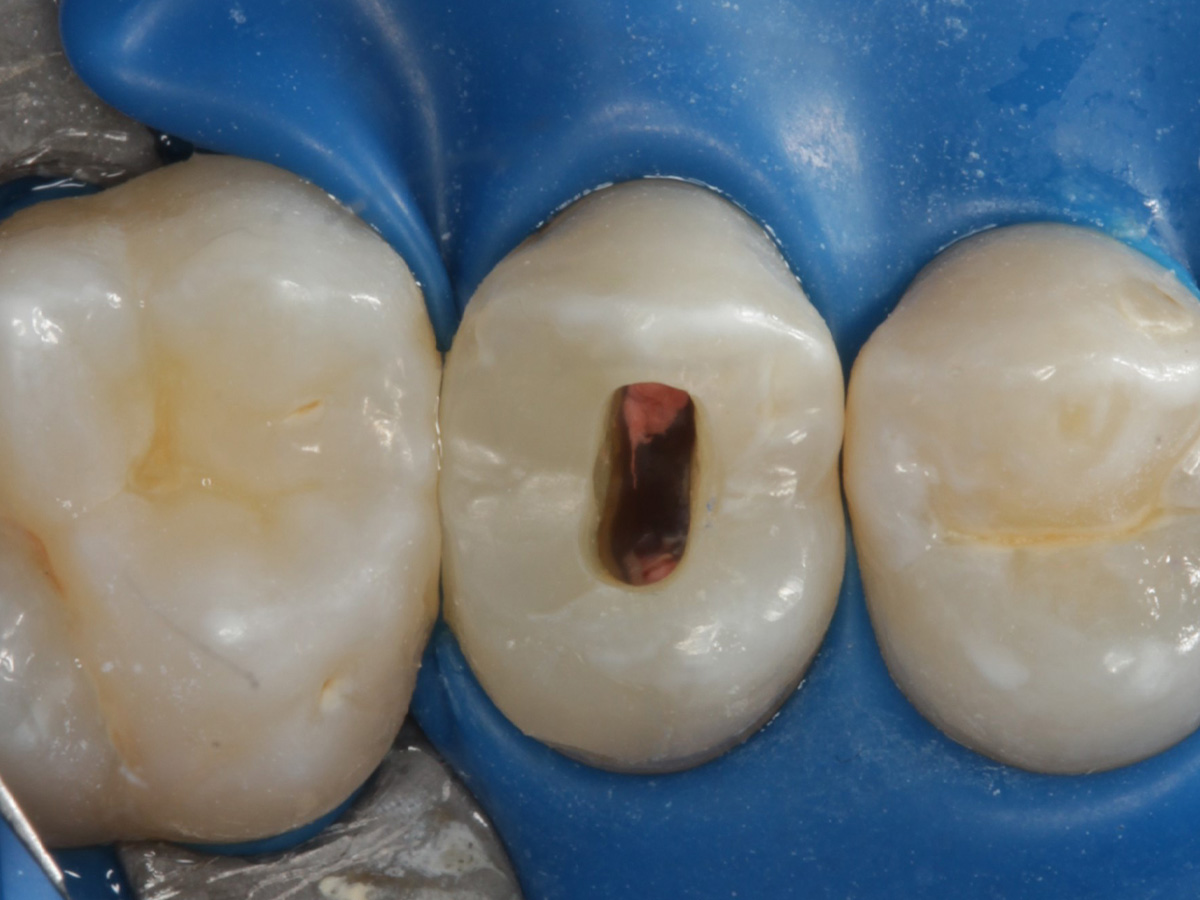

Abbildung 24

Folgesitzung: Trepanation Zahn 25

Abbildung 25

Nadelaufnahme nach elektronischer Längenmessung